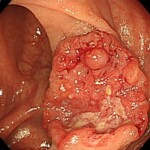

③これは②のポリープと違い明らかにがんです。こちらも早期がんであり、内視鏡治療で完治となりました。